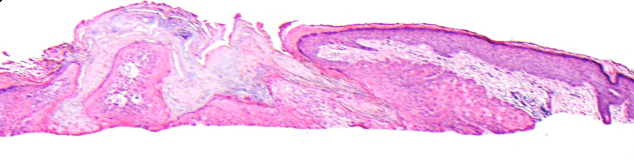

VA38: Upper Forehead, Left of Midline, Actinic Keratosis, Hypertrophic

- Arrows indicate base of epidermal thickening

VA36: Upper Forehead, Left of Midline, Adjacent, Normal